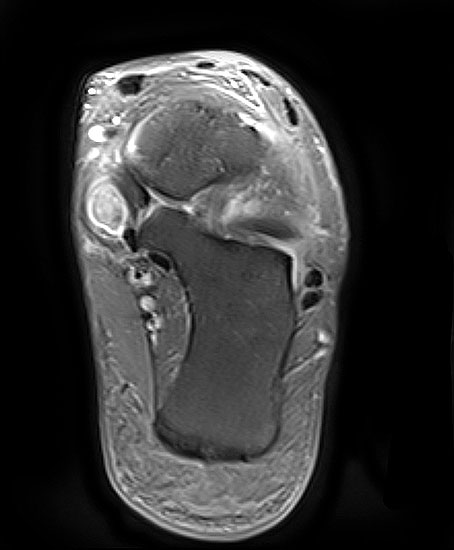

Magnet-Resonanz-Tomographie

Rupturierte Tibialis posterior Sehne in den coronaren, protonensensitiven Schichten. Bei diskreten Läsionen erhöht die Gabe von Kontrastmittel die Beurteilbarkeit.

Abbildung 6g

Die Magnet-Resonanz-Tomographie (MRT) eignet sich besonders zur Darstellung der Tenosynovitis und Degeneration der Tibialis posterior Sehne. Hinsichtlich Sensitivität und Spezifität ist das MRT dem CT insbesondere bei Sehnenlängsrupturen überlegen 23. Die normale Sehne erscheint auf dem MRT mit schwarzem, homogenem Signal und ovaler Form, zwei bis dreimal dicker als die Sehne des M. flexor digitorum longus. Ein schmaler Flüssigkeitsaum < 1-2 mm ist physiologisch. Bei der Tenosynovitis ist der Saum deutlich breiter und neben dem Ödem in der Sehnenmatrix am besten auf den T2-Wichtungen zu erkennen. Strukturelle Veränderungen der Sehnenmatrix, wie z.B. Partial- oder Längsrupturen sind besser auf den T1-Wichtungen zu sehen. Nach der Sehnenhypertrophie im Stadium I der Erkrankung kommt es jeweils mit wenig oder keiner Begleitentzündung im Stadium II zur Elongation und Abnahme des Sehnendurchmessers und im Stadium III zur Ruptur, welche im MRT gut ersichtlich sind. Hingegen finden sich mit zunehmender Dauer der Erkrankung Entzündungszeichen infolge fibulocalcanearen Impingements und lateral betonter OSG-Degeneration und Arthrose v.a. auf den T2-Wichtungen.

Weitere begleitende Befunde, die mit der Planovalgus Deformität einhergehen, sind Fibrose im Sinus tarsi, fehlende Ligamenti interosseus und cervicalis und eine fettige Degeneration des Tibialis posterior Muskels. Für die Operationsplanung ebenfalls wichtig ist die MRT Beurteilung des Ligamentum calcaneonaviculare mediale und inferiore (Spring ligament).